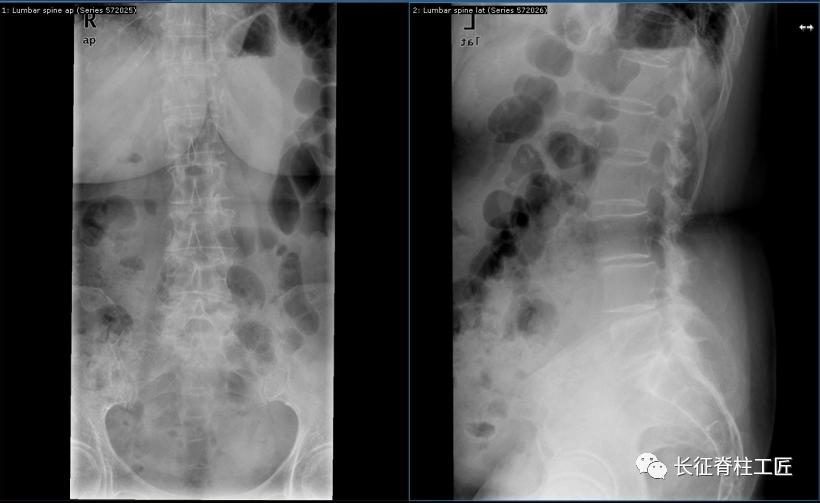

入院检查,腰部疼痛,后伸时加剧,局部压痛,双下肢肌力减退。X线检查,L4、L5骨质增生,MRI显示L4/L5、L5/S1椎间盘突出,马尾神经受压明显,被确诊为腰椎管狭窄症。